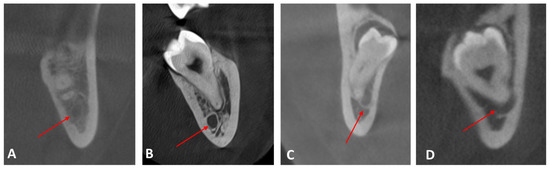

| No contact | 167 | 66.0 |

| Contact with complete white line | 27 | 10.7 |

| Contact with a defective white line | 56 | 22.1 |

| Penetration of the mandibular canal | 3 | 1.2 |